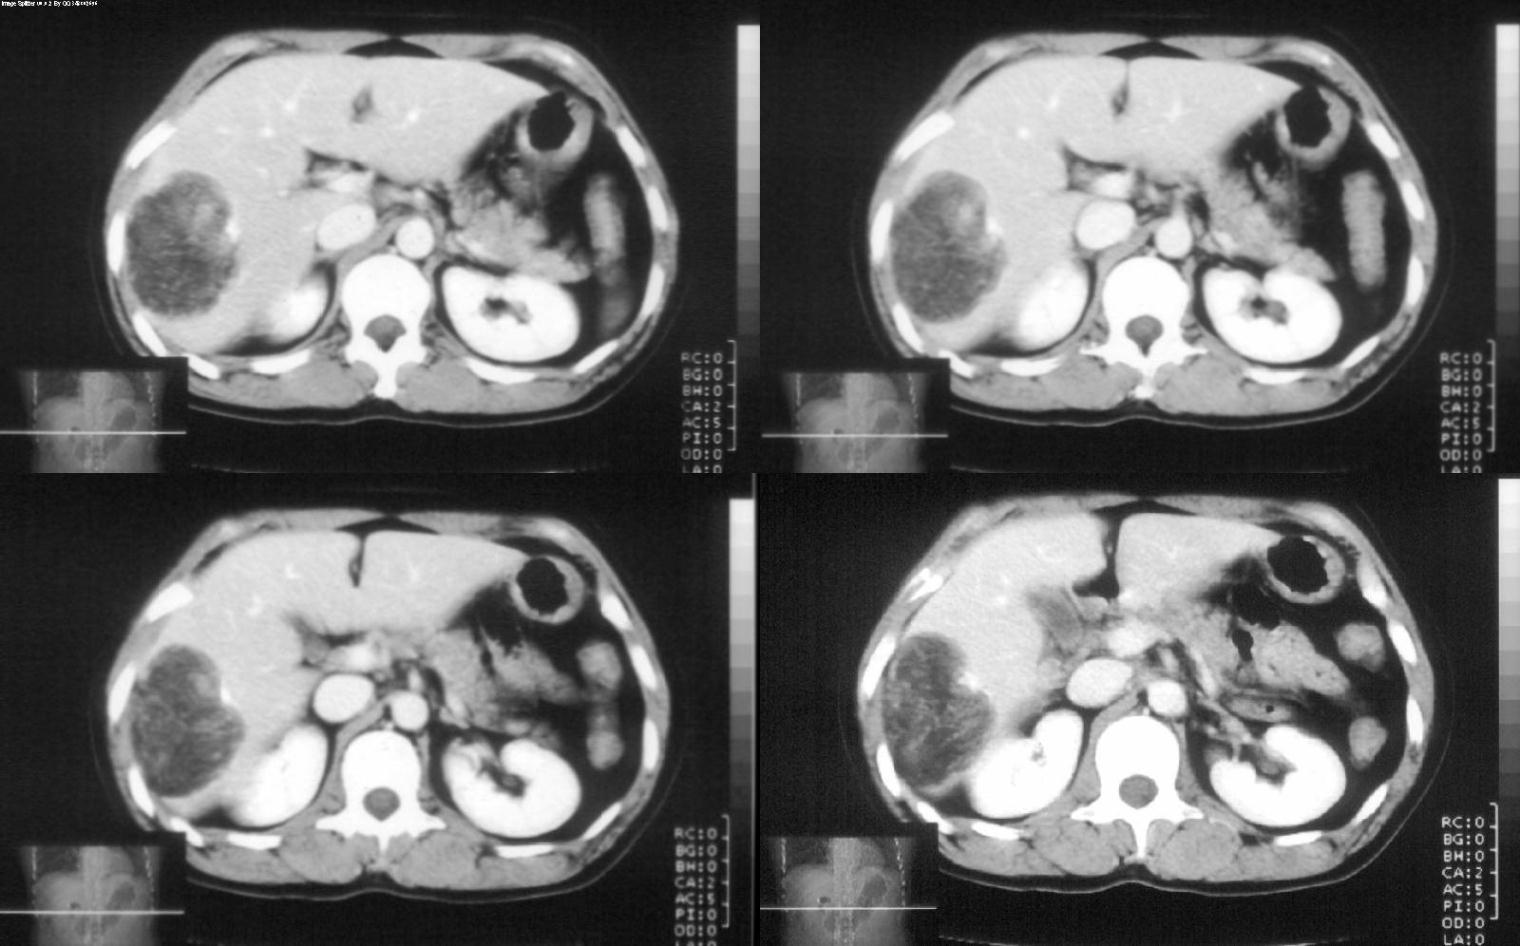

标题: CT28180:女性,42岁。体检时发占位。 [打印本页]

标题: CT28180:女性,42岁。体检时发占位。

支持 肝右叶血管平滑肌脂肪瘤。

病灶多种成分,以脂肪为主,可见强化的血管肌肉成分,边界较清晰,综合考虑血管平滑肌脂肪瘤可能性大

考虑血管平滑脂肪瘤,不能完全除外脂质丰富的肝癌